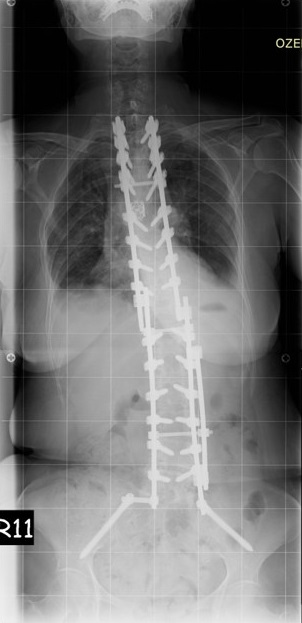

63 Yaşında Kadın Hasta

Ameliyat Sonrası